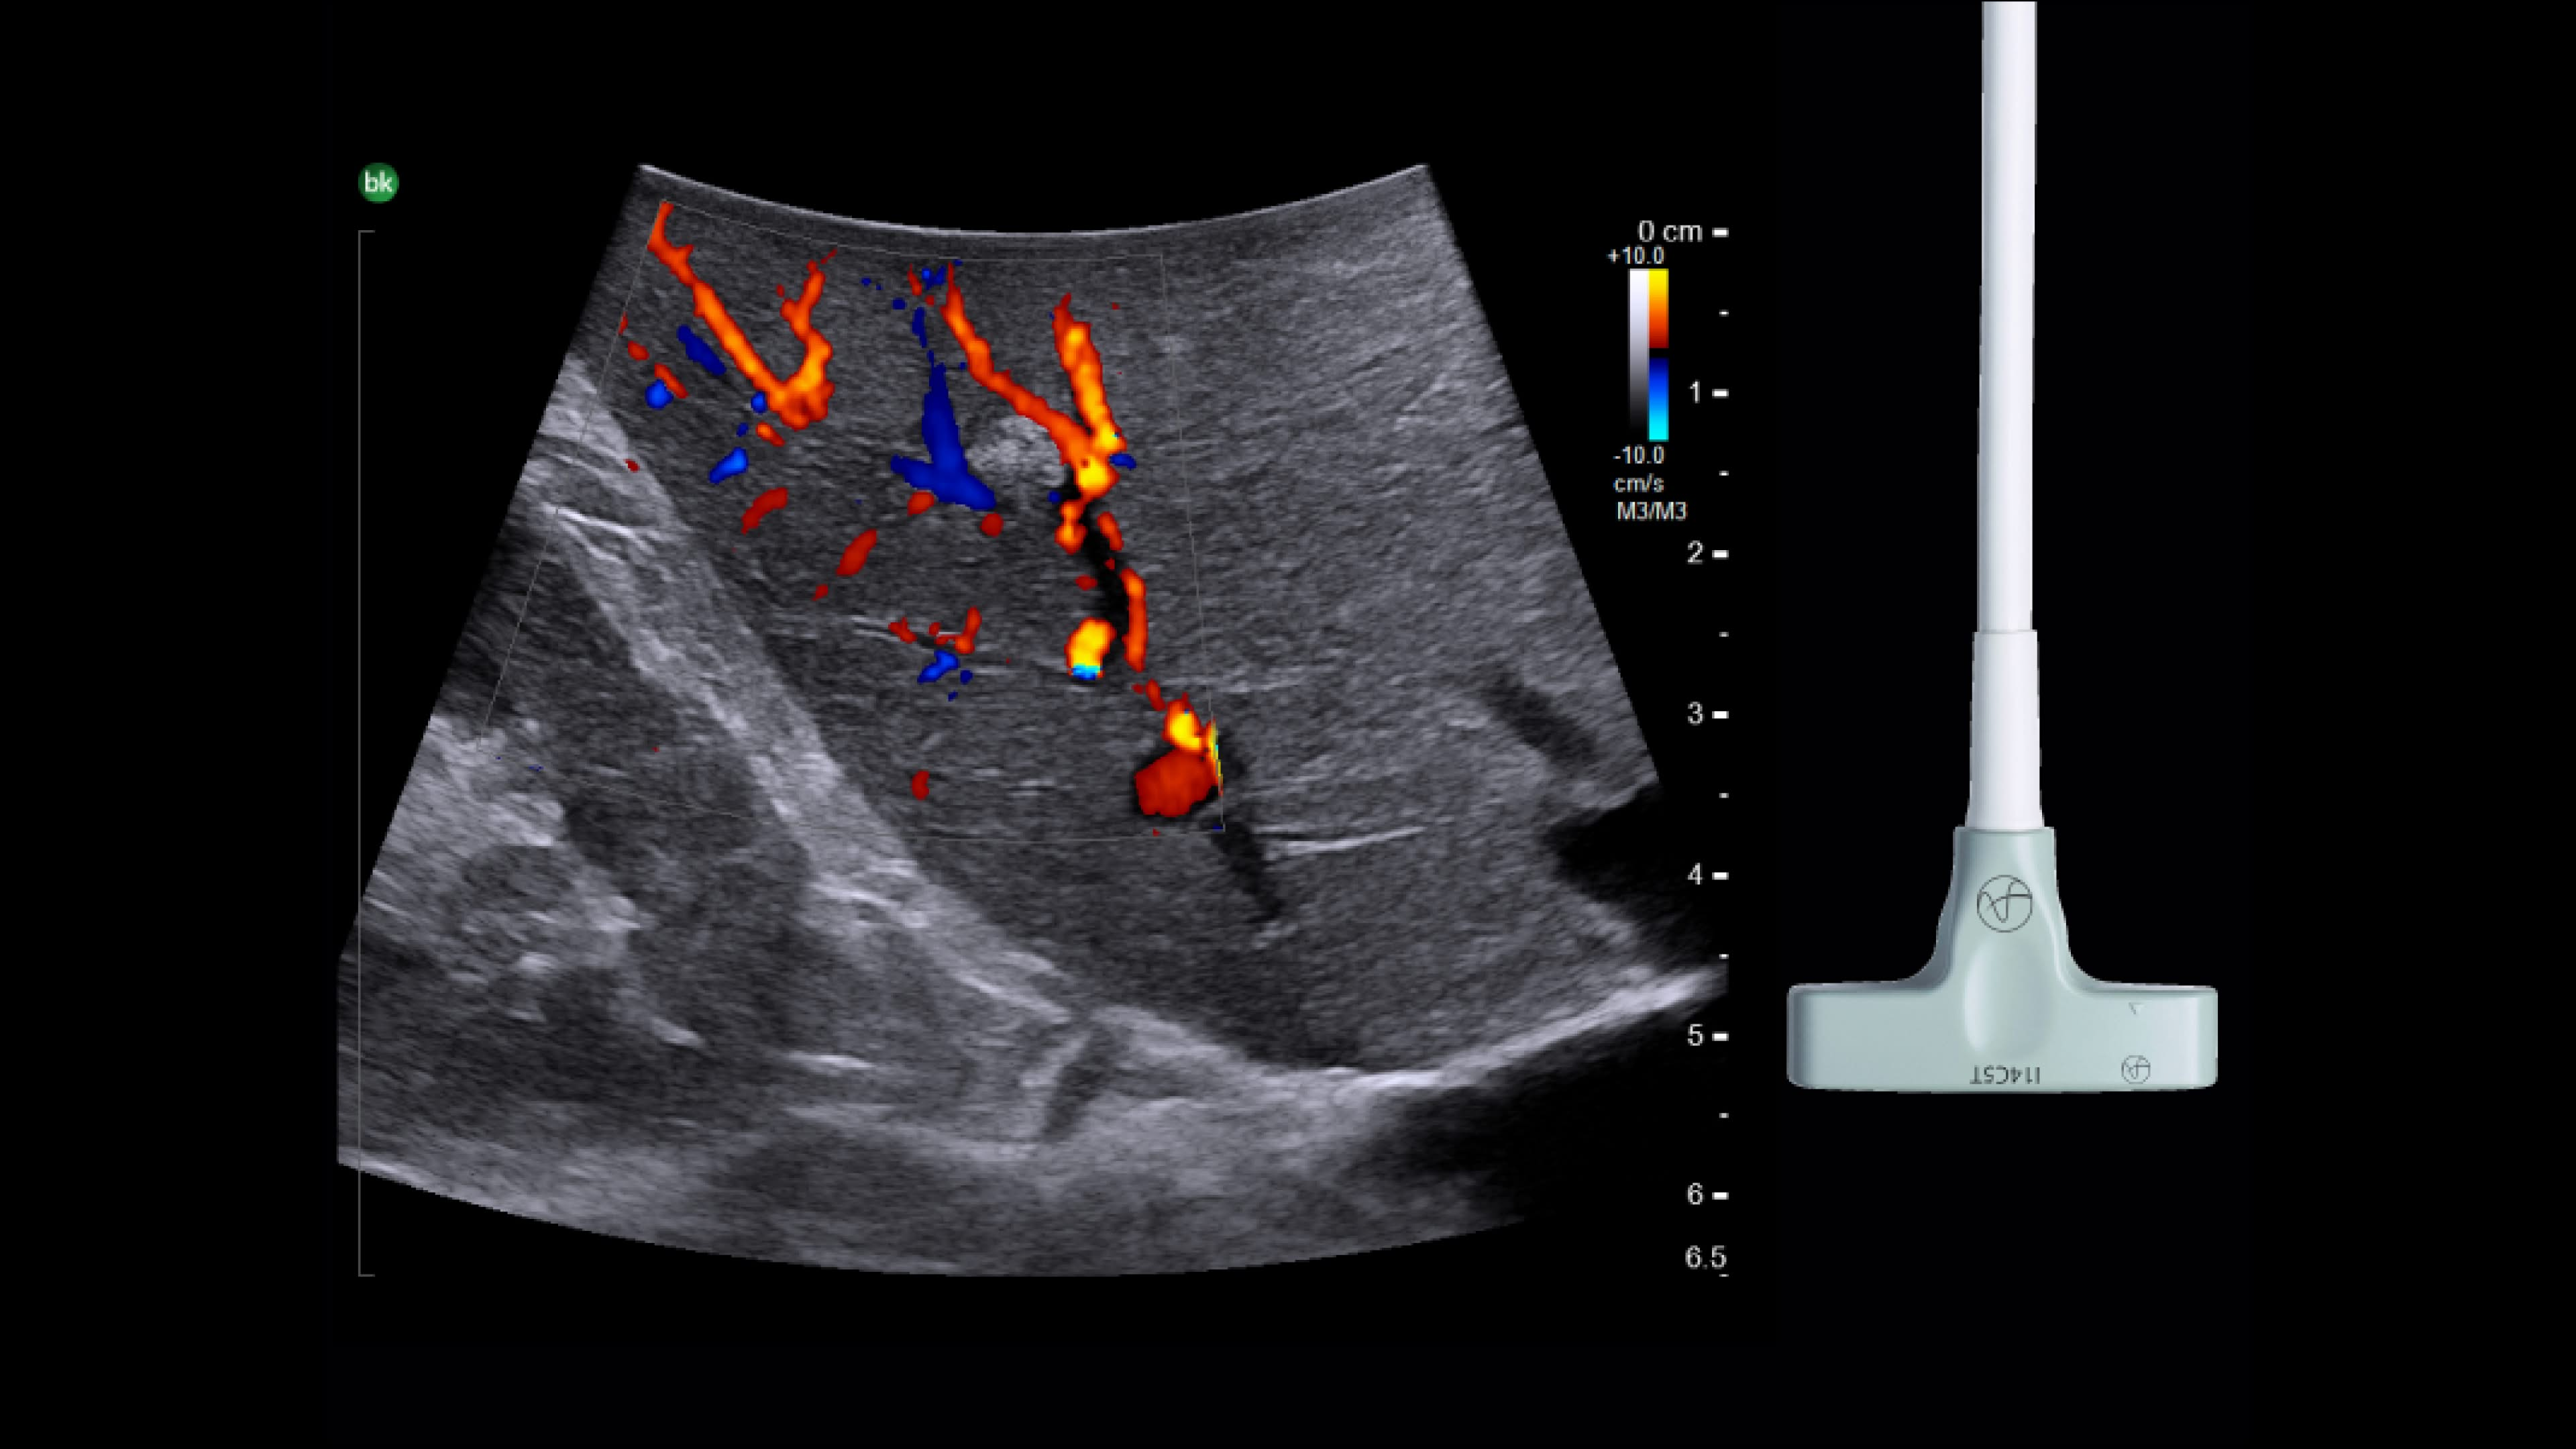

Active imaging supports liver and pancreas ablation procedures by helping you visualize lesions and blood vessels, identify healthy tissue vs. tumor, and guide and view needle placements.

Use intraoperative ultrasound to:

• Enable visualization of disease staging at the time of surgery with excellent image quality.

• Guide and view needle placements in real-time.

• Verify your planned results by assessing pre- and post-ablation images together.

Advanced Laparoscopic Transducer I13C3f*

• Plan and target tumor biopsies and ablations with patented laser technology.

• Achieve preferred insertion angle on up to two needles with proprietary channel design.